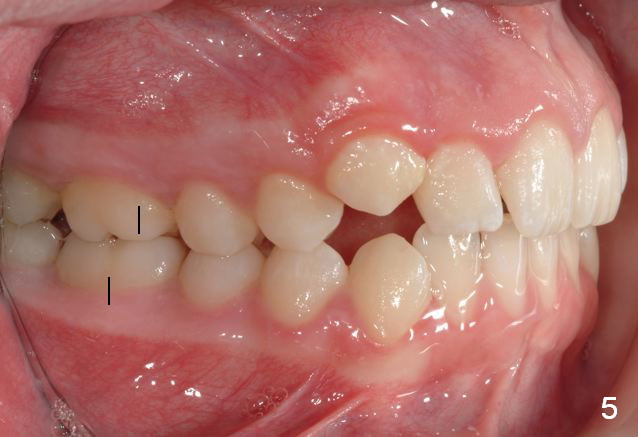

Unilateral Class II Malocclusion

The upper dental midline deviates to the left (Fig.2,4). Facial profile is normal (Fig.3). The right molar relationship is Class II (Fig.5), while the left one is normal or slightly Class III (Fig.6). How to treat?